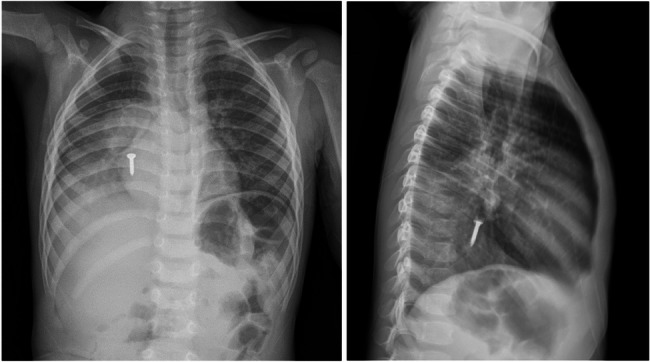

Results: Among 297 pediatric patients with FBA, 39 (13.1%) required hospitalization. Hospitalized children were younger (median age: 3 years; interquartile range [IQR] 2-7) compared with non-hospitalized children (median age: 4 years; IQR 3-7, p = 0.018). FBA involving the larynx-trachea-bronchus significantly increased the likelihood of admission (adjusted odds ratio [AOR] = 22.0; 95% confidence interval [CI]: 6.64-72.63; p < 0.001). Delayed presentation to the emergency department more than two hours after onset was also associated with hospitalization (OR = 2.77; 95% CI: 1.08-7.09; p = 0.033). Although rigid bronchoscopy remained the mainstay treatment, flexible bronchoscopy was successfully utilized in nine cases. Notably, a novel technique using a 3 mm gold-plated neodymium magnet under fluoroscopic guidance enabled the safe retrieval of distal metallic foreign bodies. Complete removal of the aspirated objects was achieved in all patients; however, one patient died following prolonged hypoxia prior to hospital arrival.